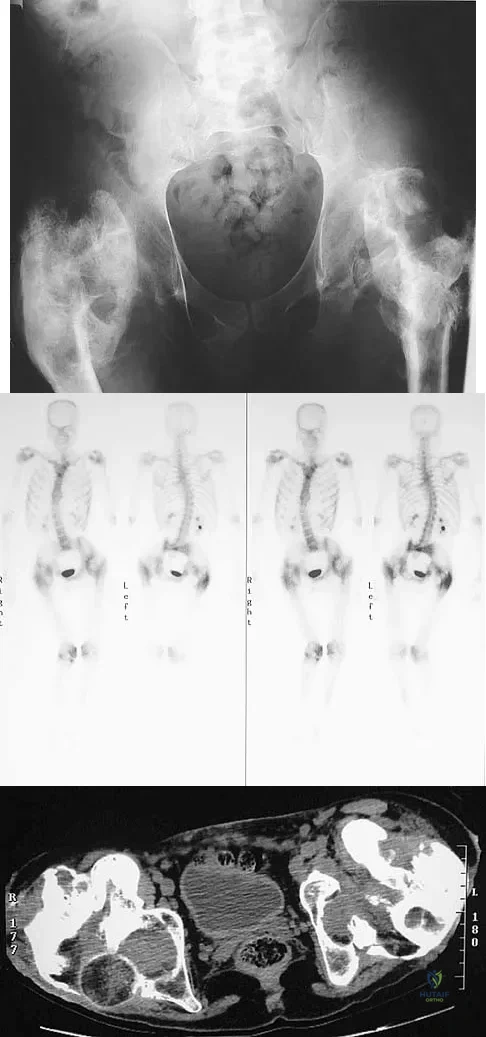

Question 17

Figure 11a shows the AP pelvis radiograph of a 25-year-old man who sustained a spinal cord injury 10 years ago. A bone scan and a CT scan are shown in Figures 11b and 11c. To prevent recurrence after resection, management should consist of

Explanation